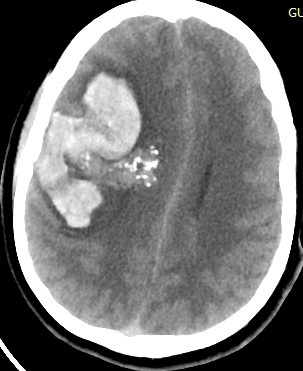

Родители нашли своего сына дома в полубессознательном состоянии. Левая сторона тела была парализована. Пять лет назад еще в подростковом возрасте у пациента обнаружили сложную врождённую патологию сосудов мозга — АВМ (артерио-венозная мальформация).

«К сожалению, вовремя пациенту не было предложено хирургическое лечение. В большинстве случаев только оно на самом деле позволяет удалить АВМ радикально и вместе с ним убрать риск кровоизлияния в мозг. Все остальные методы важны, но редко дают тот истинный долгосрочный эффект, который нужен пациентам, чтобы жить без страха кровоизлияния. И у нашего пациента оно всё-таки произошло… Уже через несколько часов от начала симптомов он оказался на операционном столе. В этот момент появились признаки, что ситуация близка к катастрофе и из-за резкого повышения внутричерепного давления возможен летальный исход еще до операции, поэтому действовать необходимо было быстро», — рассказал врач.

Сначала удалили гематому, чтобы стабилизировать ситуацию и убрать угрозу жизни пациента. На следующий день специалист эндоваскулярного отделения Республиканской больницы выполнил ангиографию сосудов и введение специального клея в сосуды АВМ для подготовки к основному хирургическому этапу.

Третьим этапом с помощью микрохирургической техники доктор Кивелёв выполнил тотальное удаление АВМ открытым способом. Пациента после нескольких дней медикаментозной комы постепенно пробудили и через неделю перевели из палаты интенсивной терапии в нейрохирургический стационар.

Контрольные снимки подтвердили радикальное удаление АВМ. Пациент в течение всего пары недель стал самостоятельно ходить и от тотального паралича левой половины тела осталась лишь незначительная слабость в левой руке.